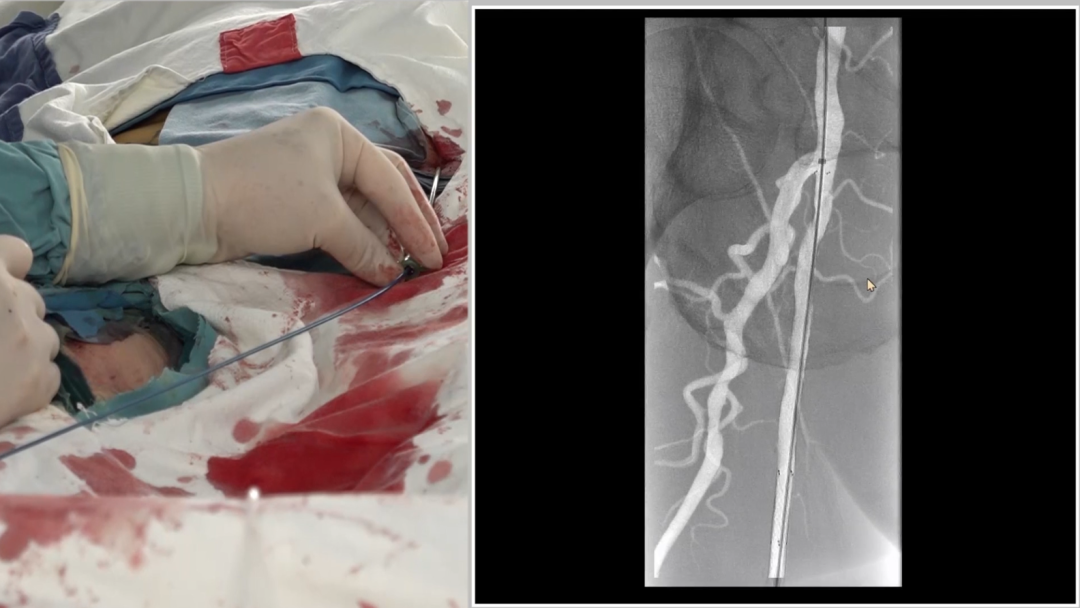

管腔准备与支架植入

预扩张:使用球囊扩张病变段,造影提示长段限流性夹层,需支架覆盖

治疗模式:因股腘动脉直径<4.5mm,选择DCB(药物涂层球囊)+BMS(裸金属支架)联合方案;

支架选择:在DCB扩张导管进行管腔准备后,植入2枚5mm INNOVA支架,其优势在于尾端定位精准,尤其适合累及开口或分叉的病变。

手术结果:

血流通畅,解剖与功能双重改善

最终造影显示:支架定位准确、形态良好,股浅动脉、腘动脉及膝下动脉显影清晰,血流通畅。